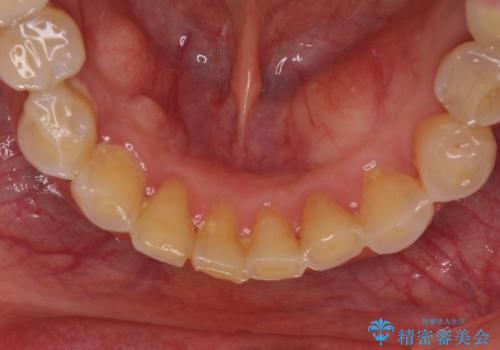

- 全顎的な歯肉からの出血と前歯の形態を気にして来院された患者様です。

診査の結果、上顎奥歯を中心に深い歯周ポケットが認められたため、歯周ポケット除去を目的とした歯周外科処置を行うこととしました。

また、前歯のブリッジへの咬合力の負担が大きく、土台となっている歯が揺れてしまっていたため、インプラント埋入により奥歯への負担を軽減することとしました。

歯周外科処置を行ったことで歯周ポケットはなくなり、毎回のブラッシングの度に嫌な思いをしていた出血は認められなくなりました。

上下前歯の見え方を気にされており、歯だけをみると大変長くなりましたが、笑ったときの口元は自然な外見となり、患者様には大変満足していただきました。